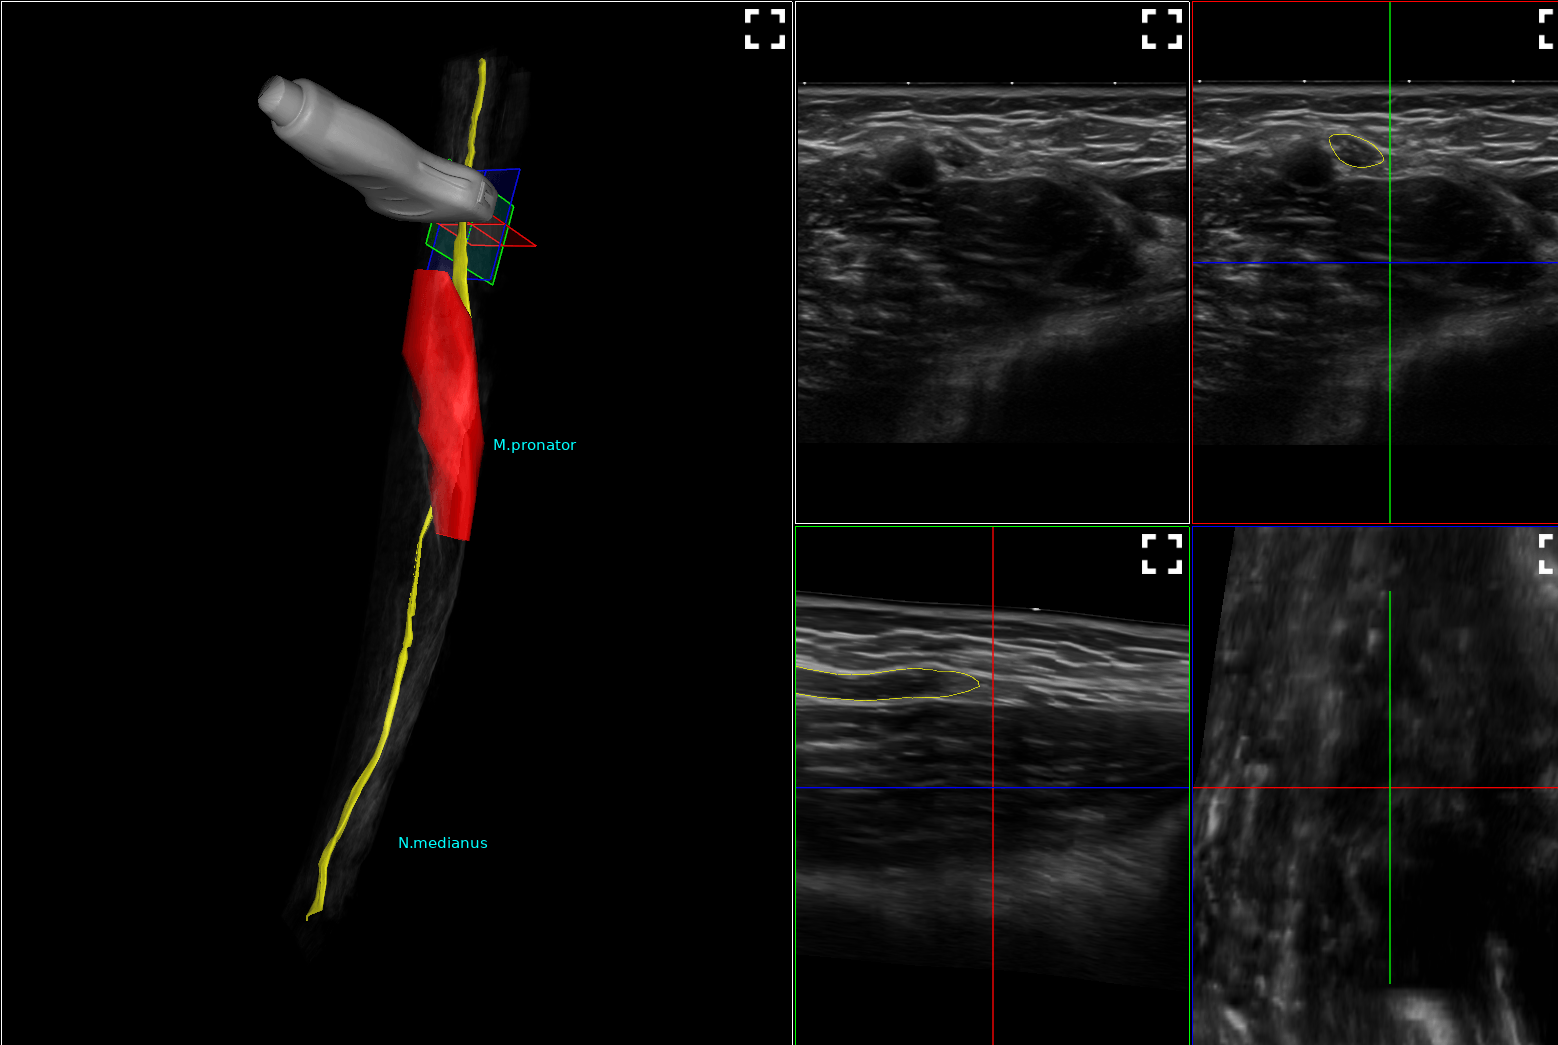

Heute wurde in unserer Praxis das weltweit erste mobile System zur 3-dimensionalen Darstellung von Nervenbahnen installiert. Hiermit können wir Veränderungen an Nerven noch präziser und v.a. anschaulich darstellen. Zudem können die Bilddaten exportiert und Ihnen mitgegeben werden (in Kooperation mit dem Hersteller in Vorbereitung), damit auch Kollegen wie z.B. Chirurgen sich ein noch besseres Bild machen können.

Mit unserm neuen hochauflösenden Clarius L15 ist Ultraschall für alle Indikationen nun auch mobil in unserer Praxis verfügbar. Zusammen mit unseren beiden Hig-End Geräten Canon aplio 300 und aplio A sowie unserem PIUR infinity für 3D/ tomographischen Ultraschall sind dem Ultraschall in unserer Praxis nun wirklich keine Grenzen mehr gesetzt.